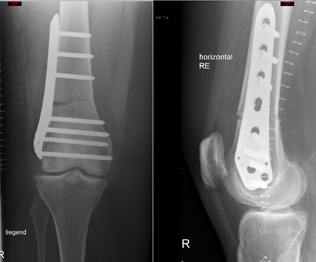

Distale Femurosteotomie (Oberschenkel), Tomofix, Depuy Synthes rechts

Beispiel einer distalen Femurosteotomie mit Tomofix-Plattensystem. Die oberen Bilder entsprechen der MRI-Bildgebung, im oberen linken Bild ist durch den roten Pfeil ein Knochenödem am Unterschenkel markiert. In der Ganzbeinaufnahme ist zu sehen, wie aus dem X-Bein ein O-Bein wurde. Die mechanische Beinachse (rot) wurde vom Aussengelenk in das Innengelenk des Knies verlagert.